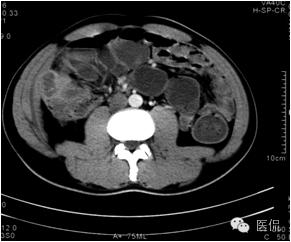

动脉期病灶显示小片状低密度影内,见不规则环状、核心样点状和间隔轻度强化,形态多种。